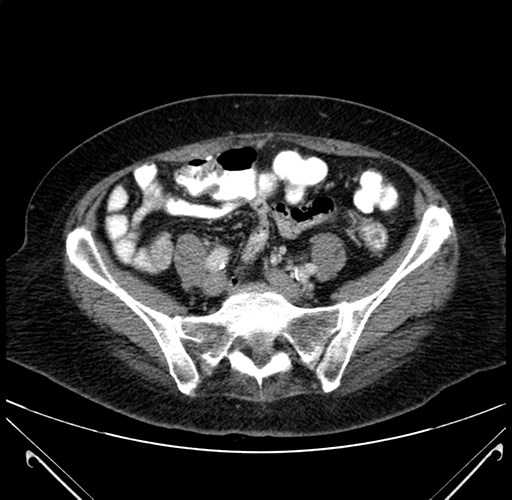

Pre-Chemo: Axial Venous